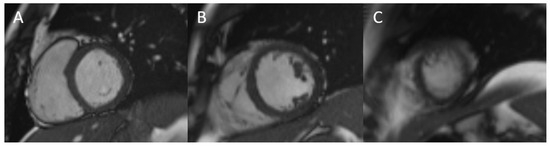

- Matusik, P.S.; Bryll, A.; Matusik, P.T.; Popiela, T.J. Ischemic and non-ischemic patterns of late gadolinium enhancement in heart failure with reduced ejection fraction. Cardiol. J. 2021, 28, 67–76. [Google Scholar] [CrossRef]